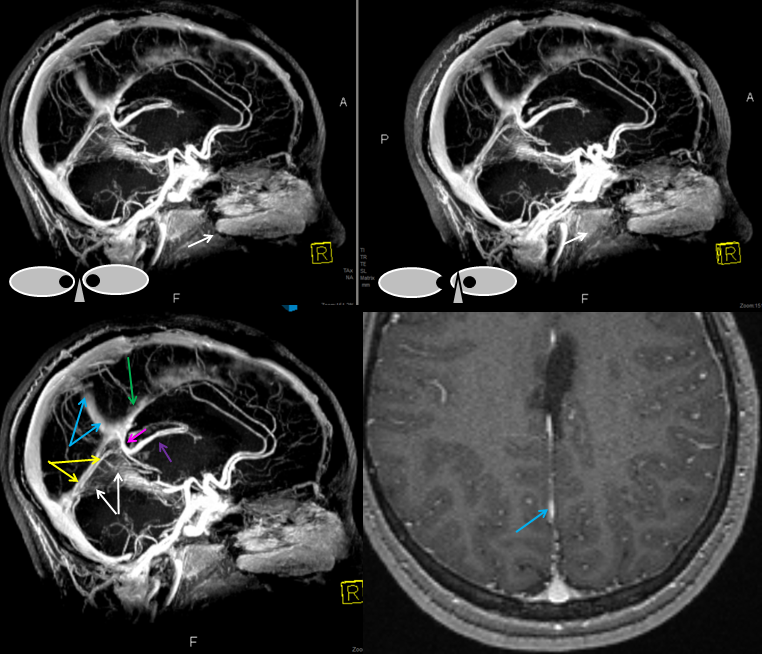

Following embolization, resection, recurrence (as frequently the case with childhood AVMs) and gamma-knife, things look good. Stereo, of course.

Following embolization, resection, recurrence (as frequently the case with childhood AVMs) and gamma-knife, things look good. Stereo, of course.